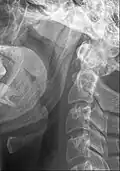

-

Ossified stylohyoid ligament or elongated styloid process